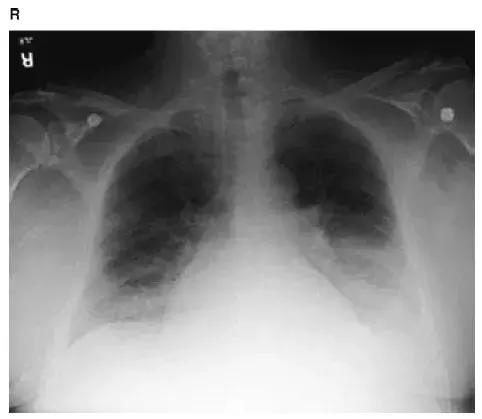

图4-19 胸片显示双肺网状结节阴影,肺体积缩小,病理上符合普通型间质性肺炎(UIP);临床上UIP通常指的是特发性肺纤维化(IPF)

图4-20 CT显示普通间质性肺炎(UIP),即特发性肺纤维化(IPF):典型的表现包括牵拉性支气管扩张(黑箭头)和蜂窝肺(红箭头);蜂窝肺主要分布于胸膜下、基底部